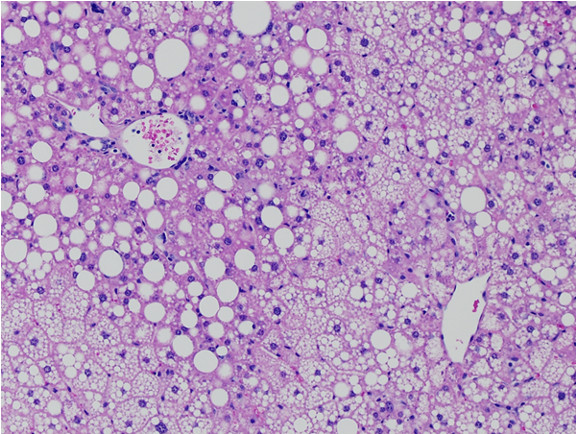

Figure 6: Histopathology for C57BL/6NTac mice placed on D09100310 diet (MASH B6NTac) or kept on chow diet (Control B6NTac) from 6 weeks of age. Animals were on diet for 27, 35 or 53 weeks. Hematoxylin and eosin (H&E) staining illustrates morphological changes including steatosis and infiltration of immune cells. Activated HSCs were identified in liver sections by using a rabbit polyclonal antibody to alpha-smooth muscle actin (a-SMA) (1:500 dilution; ab5694; Abcam, Cambridge, MA) which was detected by an anti-rabbit IgG embedded polymer with embedded horseradish peroxidase and visualized with 3,3′-diaminobenzidine (DAB) chromogen (Agilent, Carpentaria, CA). Hepatocellular lipid droplets were identified by visualization of the lipid-binding protein adipophilin known to be expressed in steatotic livers. Sections of livers were probed using a rabbit polyclonal anti-adipophilin antibody (1:200 dilution; NB110-40877, Novus Biologics, Littleton, CO) which was detected by an anti-rabbit IgG embedded polymer with embedded horseradish peroxidase and visualized with 3,3′-diaminobenzidine (DAB) chromogen (Aligent, Carpentaria, CA). Picrosirius red (PSR) staining illustrates collagen I and III fibers and is used to measure fibrosis. The same individual MASH or control animal is shown for all four stains in a particular time point. Different individual animals were used for each time point (i.e. data is not longitudinal by animal). Histopathology services provided by IDEXX BioAnalytics.